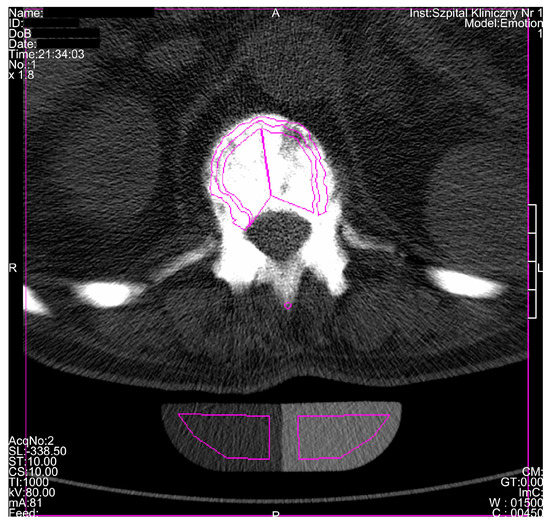

3. Results

| Radiological Feature | ADO Type I | ADO Type II | ADO Type III | Presented Case |

|---|---|---|---|---|

| General osteosclerosis | + | – | + | + |

| Skull vault osteosclerosis | + | – | + | + |

| Skull base osteosclerosis | – | + | – | + |

| Sandwich vertebrae (Ruger–Jersey spine) | – | + | – | + |

| Bone within bone | – | + | + | + |

| Hyoid sclerosis | – | – | – | + |